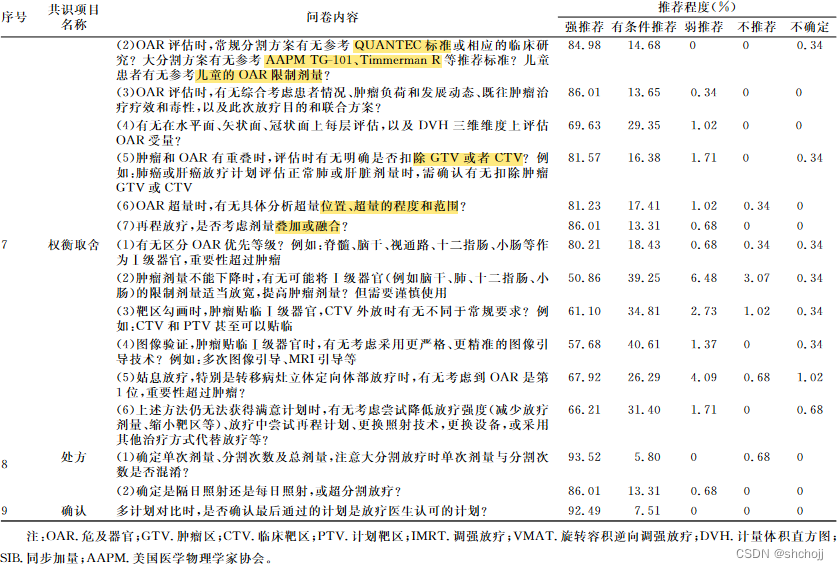

6、OAR保护

7、权衡取舍

8、处方剂量(RxDose)

9、确认